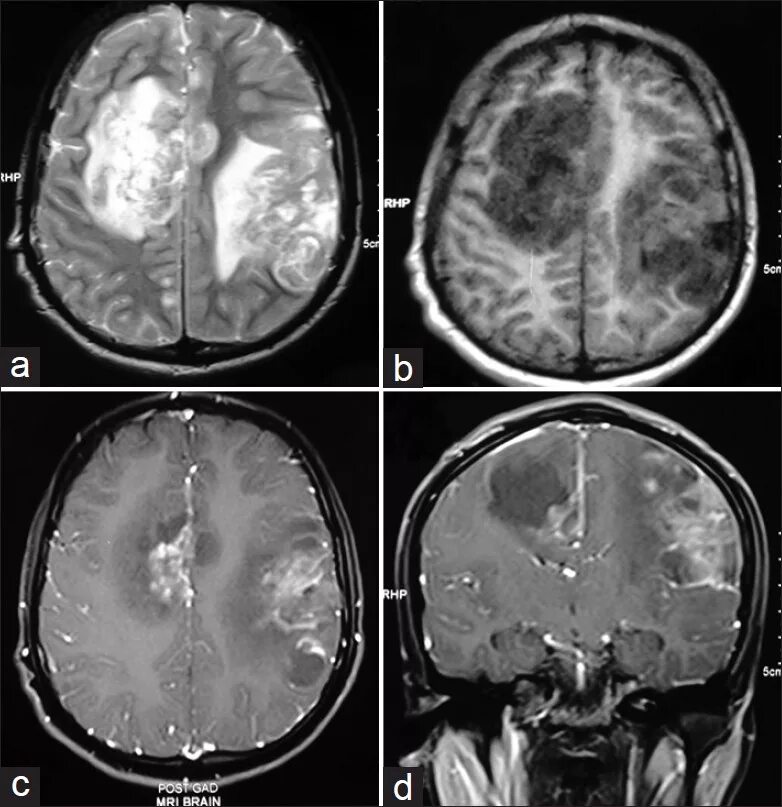

Гематома лобной